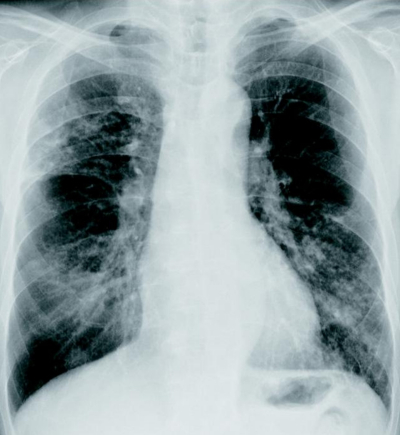

71 歳の男性。血痰を主訴に来院した。2か月前から微熱があり、2週前から断続的に血痰の排出が続いている。かかりつけ医で糖尿病の内服加療中であるが、コントロールは良くないと言われているという。呼吸音は両側胸部に coarse cracklesを聴取する。胸部エックス線写真及び胸部造影 CTを別に示す。

亜急性の経過、血痰、画像所見、糖尿病による易感染により肺結核の可能性を考える必要あり。